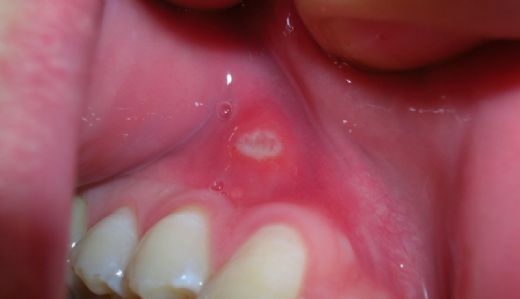

Ağız İçi Yarasına Ne İyi Gelir?

Ağzı içi yaraları, çeşitli nedenlerle oluşabilen acı verici lezyonlardır ve yaşam kalitesini olumsuz etkileyebilir. Bu yazıda, yaraların nedenleri, belirtileri ve doğal ile tıbbi tedavi yöntemleri hakkında kapsamlı bilgi sunulmaktadır. Ağzı içi yaralarına dair bilinçlenmek, etkili çözümler bulmak için önemlidir.

Ağzı İçi Yarasına Ne İyi Gelir?Ağzı içi yaraları, genellikle ağız içinde meydana gelen ve çeşitli nedenlerden kaynaklanan acı veren lezyonlardır. Bu yaralar, bireylerin günlük yaşam kalitesini olumsuz etkileyebilir. Bu makalede, ağız içi yaralarının nedenleri, belirtileri ve bu yaralar için etkili tedavi yöntemleri üzerinde durulacaktır. Ağzı İçi Yararının NedenleriAğzı içi yaralarının birçok nedeni olabilir. Bunlar arasında:

Ağzı İçi Yarası BelirtileriAğzı içi yaralarının belirtileri genellikle aşağıdaki gibi görülmektedir: